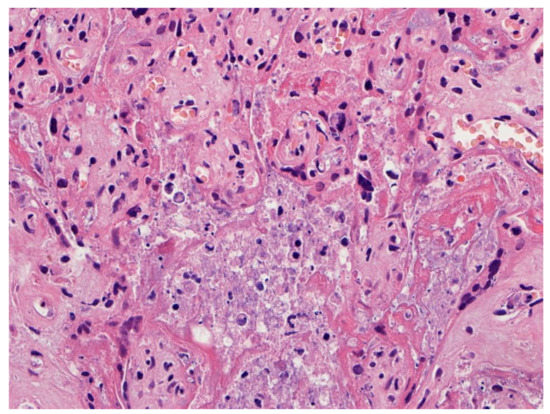

Figure 4.

Chronic histiocytic intervillositis is present demonstrating histiocytes within the remnants of the intervillous spaces in a placenta with massive perivillous fibrin deposition and trophoblast necrosis. This stillborn fetus was delivered to a mother with COVID-19. The syncytiotrophoblast of this placenta was strongly positive for SARS-CoV-2 antigens using immunohistochemistry. Hematoxylin & eosin staining, ×20.